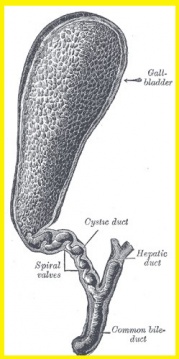

| 11:17, 27 במאי 2013 | Gallbladder14.jpg (קובץ) |  |

36 קילו־בייטים | Zvi kaufman | 2 | |

| 11:15, 27 במאי 2013 | Gallbladder6.jpg (קובץ) |  |

56 קילו־בייטים | Zvi kaufman | 2 | |

| 11:10, 27 במאי 2013 | Gallbladder5.jpg (קובץ) |  |

61 קילו־בייטים | Zvi kaufman | 4 | |

| 11:02, 27 במאי 2013 | Gallbladder4.jpg (קובץ) |  |

33 קילו־בייטים | Zvi kaufman | 2 | |

| 11:00, 27 במאי 2013 | Gallbladder3.jpg (קובץ) |  |

62 קילו־בייטים | Zvi kaufman | 2 | |

| 10:59, 27 במאי 2013 | Gallbladder2.jpg (קובץ) |  |

176 קילו־בייטים | Zvi kaufman | 2 | |

| 10:57, 27 במאי 2013 | Gallbladder1.jpg (קובץ) |  |

43 קילו־בייטים | Zvi kaufman | 2 | |

| 04:13, 23 במאי 2013 | Gallbladder13.jpg (קובץ) |  |

29 קילו־בייטים | Zvi kaufman | שוחזר לגרסה מ־04:11, 23 במאי 2013 | 5 |